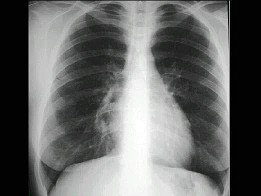

51、单项选择题

男,7岁,外伤后突发呼吸困难伴胸痛,结合图像,最可能的诊断是()